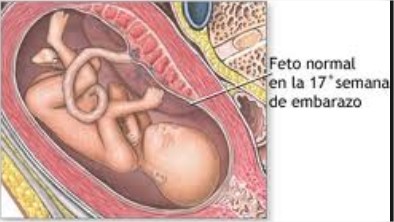

17 semanas de gravidez

O bebê nas 18 semanas de gestação tem o lanugo já à vista1. Lanugo? Sim, a fina camada de pêlos bem fininhos que cobrem o corpo do bebê! Seu pequeno amor pode estar já com 14,2 cm e pesando cerca de 190 gramas! Cresce a olhos vistos, e mais e mais a cada dia. O bebê começa a fazer os movimentos respiratórios. Mas é somente um treino, já que a placenta supre todas as necessidades de oxigenação do bebê.

Nas 18 semanas de gravidez, o grande marco que ocorre é do desenvolvimento auditivo2. O bebê já consegue escutar o coração da mamãe batendo, assim como os ruídos internos do sangue que corre pelo cordão umbilical ou do trabalhar do estômago. Dentro de alguns dias já será possível ele escutar os ruídos e vozes do lado de fora do útero, e com isso identificar a voz da mamãe.

Outro marco importante nesta semana é que o bebê já começa a simular os movimentos da respiração mesmo ainda não sendo necessário, pois ele continua somente engolindo líquido amniótico. Seus pequenos olhos já tem sensibilidade à luz e respondem a estímulos quando feitos do lado externo. Seu intestino está em fase de aperfeiçoamento e começa a produzir o mecônio (primeiras fezes) através do líquido amniótico que engole.